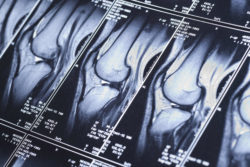

A knee replacement is a solution for many patients whose knees have worn out, but knee replacements can come with problems of their own. Many patients may not anticipate experiencing pain years after a knee replacement, but a number of conditions can cause it to occur, including aseptic loosening.

A knee replacement is a solution for many patients whose knees have worn out, but knee replacements can come with problems of their own. Many patients may not anticipate experiencing pain years after a knee replacement, but a number of conditions can cause it to occur, including aseptic loosening.

Around 10 percent of knee replacement patients are less than satisfied with the results of their knee replacement surgery. Some report pain that can come from postoperative infection or a bone fracture around the replacement, or persistent pain around a new knee replacement.

Problems that persist years after a knee replacement include a loss of mobility or range of motion, instability, chronic pain, or loosening of the knee implant.

Aseptic Loosening

When the implant loosens but does not become infected, this condition is called aseptic loosening. This can occur because the bond between the natural bone and the knee replacement has become compromised. In knee replacements in which bone cement is used to secure the implant to the natural bone, aseptic loosening can be caused by the bone cement failing.

Aseptic loosening is more common in the part of the implant that’s attached to a patient’s tibia bone. It’s less common in the femur component.